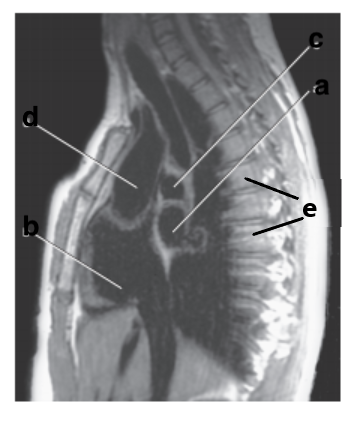

Which letter is the Descending aorta ?

f

What is letter a ?

Left Ventricle

Left atrium

Right ventricle

What is letter e ?

Vertebral body

Aortic Arch

Identify the structure labeled with "e":

Liver

What is letter c ?

Trachea

Thoracic vertebra

What is letter f ?

Sternum